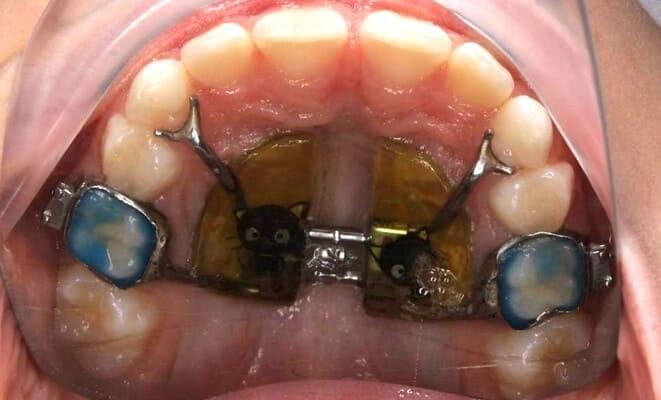

Дівчинка, 5 років. Лікування зворотнього пульпіту тимчасових зубів 85,84 та їх відновлення за допомогою стандартних металевих коронок. Лікування проводилось в умовах закису азоту кисневої седації. Період зміни зубів - 10-12 років.